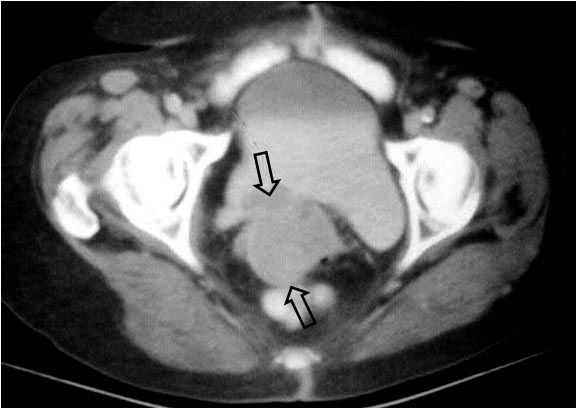

SIGNO DE LA PRÓSTATA FEMENINA

Signo visible en la urografía intravenosa o la cistografía de una mujer, correspondiente a una impresión en el suelo vesical similar a la impronta prostática del varón. Puede ser producida por lesiones neoplásicas o inflamatorias de la zona.

La imagen de TC corresponde a la misma paciente de la urografía, que presenta un tumor de cuello uterino -flechas negras- que infiltra la vejiga. Se trataba de un adenocarcinoma mucosecretor. La imagen recuerda a la impronta prostática en el TC.